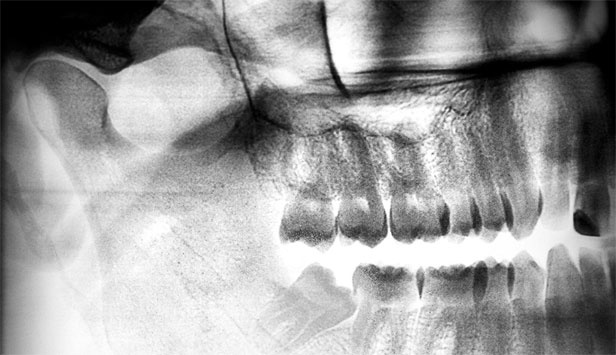

А на этом снимке наглядно видно, как «восьмерки» повреждают «семерки». Зачастую при такой ситуации уже глубокий кариес корня седьмых зубов и их приходится удалять вместе, так как, к сожалению, уже не спасти.

Не надо тянуть и дожидаться, когда зубы мудрости нанесут вред. Сделайте снимки всех зачатков восьмых зубов, и, если они расположены криво, есть смысл удалить их до окончательного формирования корневой системы.

Вот, например, какая «восьмерка» была у меня:

Иллюстрация к книге — Злые зубы [i_033.jpg]

Если на снимках зубы мудрости расположены криво, есть смысл удалить их до окончательного формирования корневой системы.

Удаление было довольно легким из-за того, что корень до конца не сформирован. А вполне возможно, что если бы я подождала еще пару лет, выросло бы что-нибудь такое и удалить это было бы гораздо сложнее: